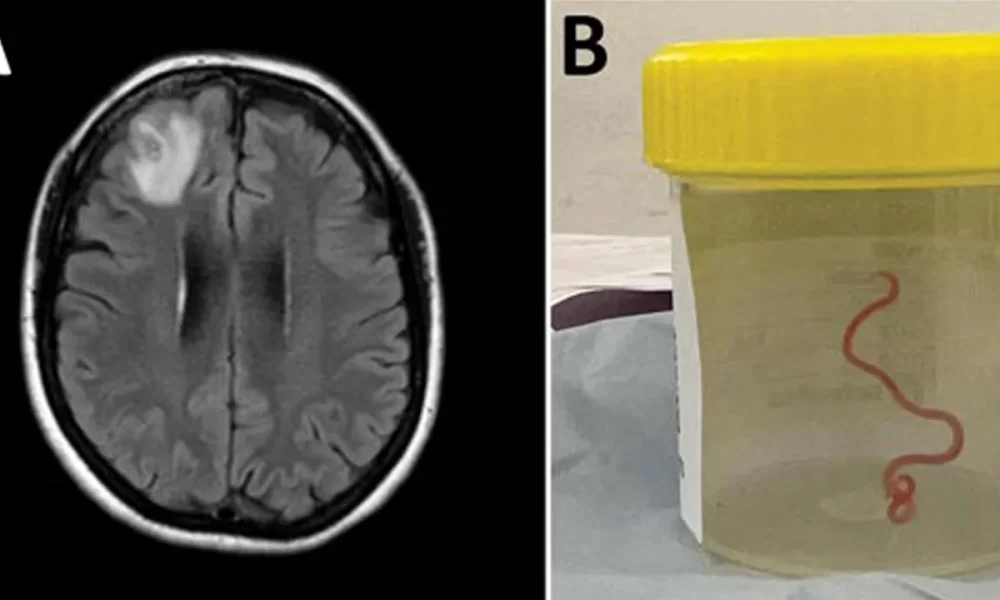

Australian doctors have found a live parasitic worm in a woman’s brain in a world-first discovery. In a new study published on Tuesday, researchers from the...